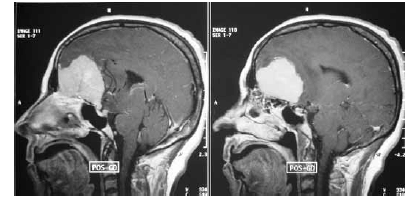

Considerando a figura acima, que mostra o resultado do exame de imagem de um paciente, julgue os itens seguintes.

A lesão identificada no exame de imagem em questão é frequente em pacientes com neurofibromatose tipo 2.